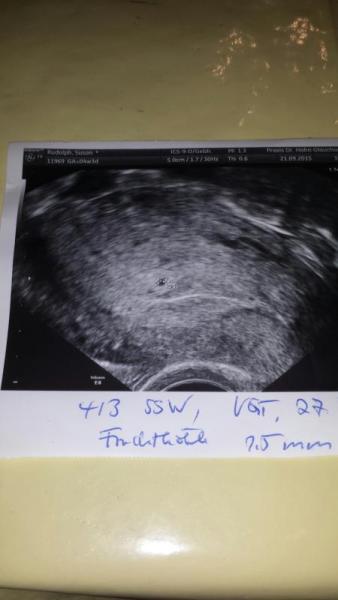

huhu. erstmal sorry das ich mich so spät melde. Danke für eure antworten. bin jetzt 6. woche und fühle mich richtig gut. habe nächste Woche wieder einen Termin zum Ultraschall. worauf ich mich sehr freue auch wenn man vielleicht nix sieht. Habe mal das allererste Bild mit hoch geladen. Ne Freundin von mir meine sie sieht jicht nur die Fruchthülle sondern auch nen weißen Schatten am Rand. Ich lege mich da aber jicht fest. weil ja bekanntlich Einbildung auch ne Bildung is &522;

Bild zu